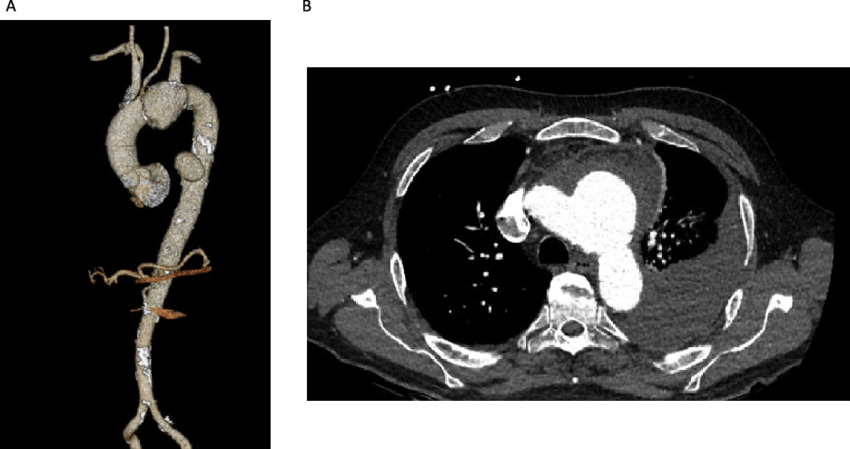

КТ-ангіографія — це сучасний метод обстеження судин, який дозволяє побачити їх стан без катетерів, розрізів і госпіталізації. Дослідження триває кілька хвилин і дає лікарю детальну 3D-картину артерій та вен у будь-якій ділянці тіла. Саме тому цей метод дедалі частіше замінює класичну інвазивну ангіографію в діагностичних цілях.

КТ-ангіографія є неінвазивним методом візуалізації судин, що дозволяє детально оцінити їх стан без необхідності хірургічного втручання. Основним принципом цього методу є болюсне контрастування, яке забезпечує чітке зображення судинної системи. Це досягається шляхом введення контрастної речовини, яка підсилює видимість судин на знімках, отриманих за допомогою комп’ютерної томографії.

Основою КТ-ангіографії є болюсне введення контрастної речовини у вену. Контраст «підсвічує» судини, і комп’ютерна томографія фіксує їх у момент максимального наповнення кров’ю. У результаті отримують чіткі пошарові зображення, які можна переглядати у різних площинах та реконструкціях.

КТ-ангіографія дозволяє виявити аневризми — патологічні розширення судин, що можуть становити загрозу розриву. Чим раніше виявлена аневризма, тим більше шансів запобігти небезпечним ускладненням. Метод також точно визначає стенози — звуження артерій, які порушують кровотік і можуть призводити до інсульту або інфаркту.

Завантажити дослідженняДослідження ефективне для діагностики атеросклерозу. КТ-ангіографія показує наявність атеросклеротичних бляшок, їх розміри та ступінь перекриття просвіту судини. Це дає можливість оцінити ризики та обрати оптимальну тактику лікування — медикаментозну терапію, стентування або хірургічне втручання.

Метод також застосовується для виявлення вроджених судинних мальформацій, тромбозів, тромбоемболії легеневої артерії та порушень мозкового кровообігу. У невідкладних ситуаціях КТ-ангіографія дозволяє швидко прийняти клінічне рішення, що може врятувати життя.